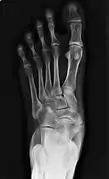

Type 2